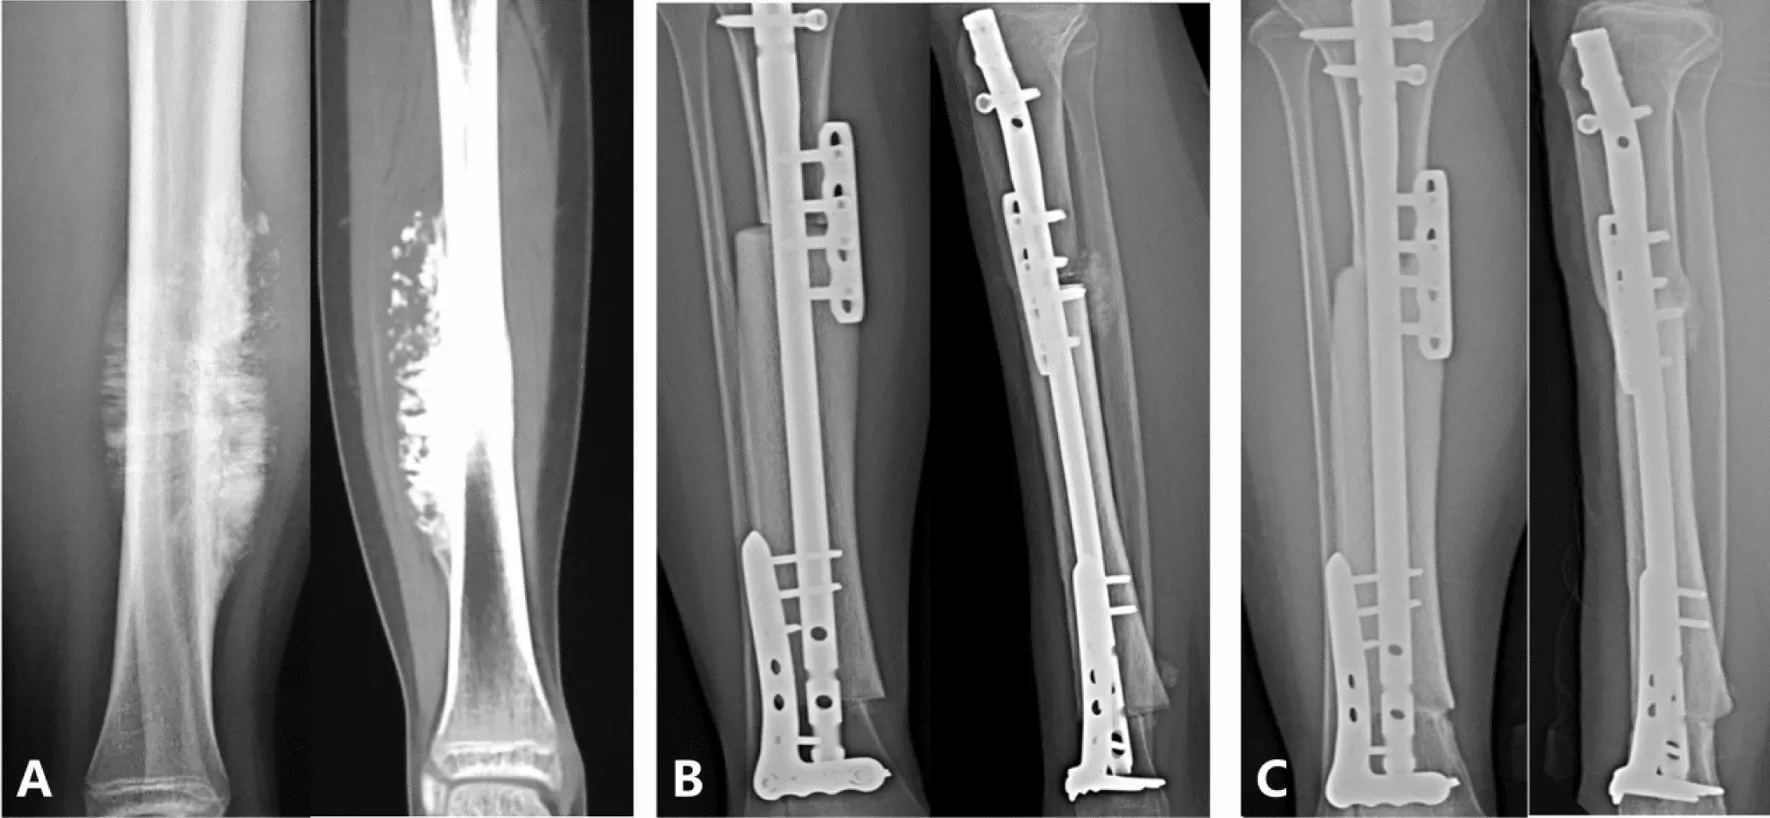

استفاده از یک پیوند آلوگرافت برای بازسازی یک نقص استخوانی حجیم (به عنوان مثال، پس از برداشتن یک تومور از استخوان فمور (femur) یا استخوان تیبیا (tibia)) یک تکنیک پیچیده اما ارزشمند است. جراح یک قطعه استخوان جسدی متناسب را که معمولاً از یک بانک استخوان تهیه میشود، به شکلی که جایگزین بخش برداشته شده شود، شکل میدهد. پیوند آلوگرافت با ابزارآلات فلزی (پلاکها، پیچها، و میلههای درونمغزی) در جای خود تثبیت میشود و گاهی با پیوندهای استخوانی کوچک خود بیمار ترکیب میشود تا به بهبودی کمک کند. با گذشت زمان، انتظار میرود که استخوان بیمار با آلوگرافت در محلهای اتصال جوش بخورد و خود آلوگرافت نیز با عروقسازی مجدد از میزبان، به تدریج بازسازی شود. این روش در تضاد با جایگزینی درونپروتزی است، که در آن یک ایمپلنت فلزی جایگزین استخوان و مفصل میشود.

شکل: نمونهای از بازسازی بزرگ استخوان تیبیا (tibia) با آلوگرافت در یک بیمار ۱۴ ساله مبتلا به استئوسارکوما. تصویر منتشر شده از ژورنال “Journal of Orthopaedics and Traumatology”

مزیت اصلی یک پیوند آلوگرافت در نجات عضو